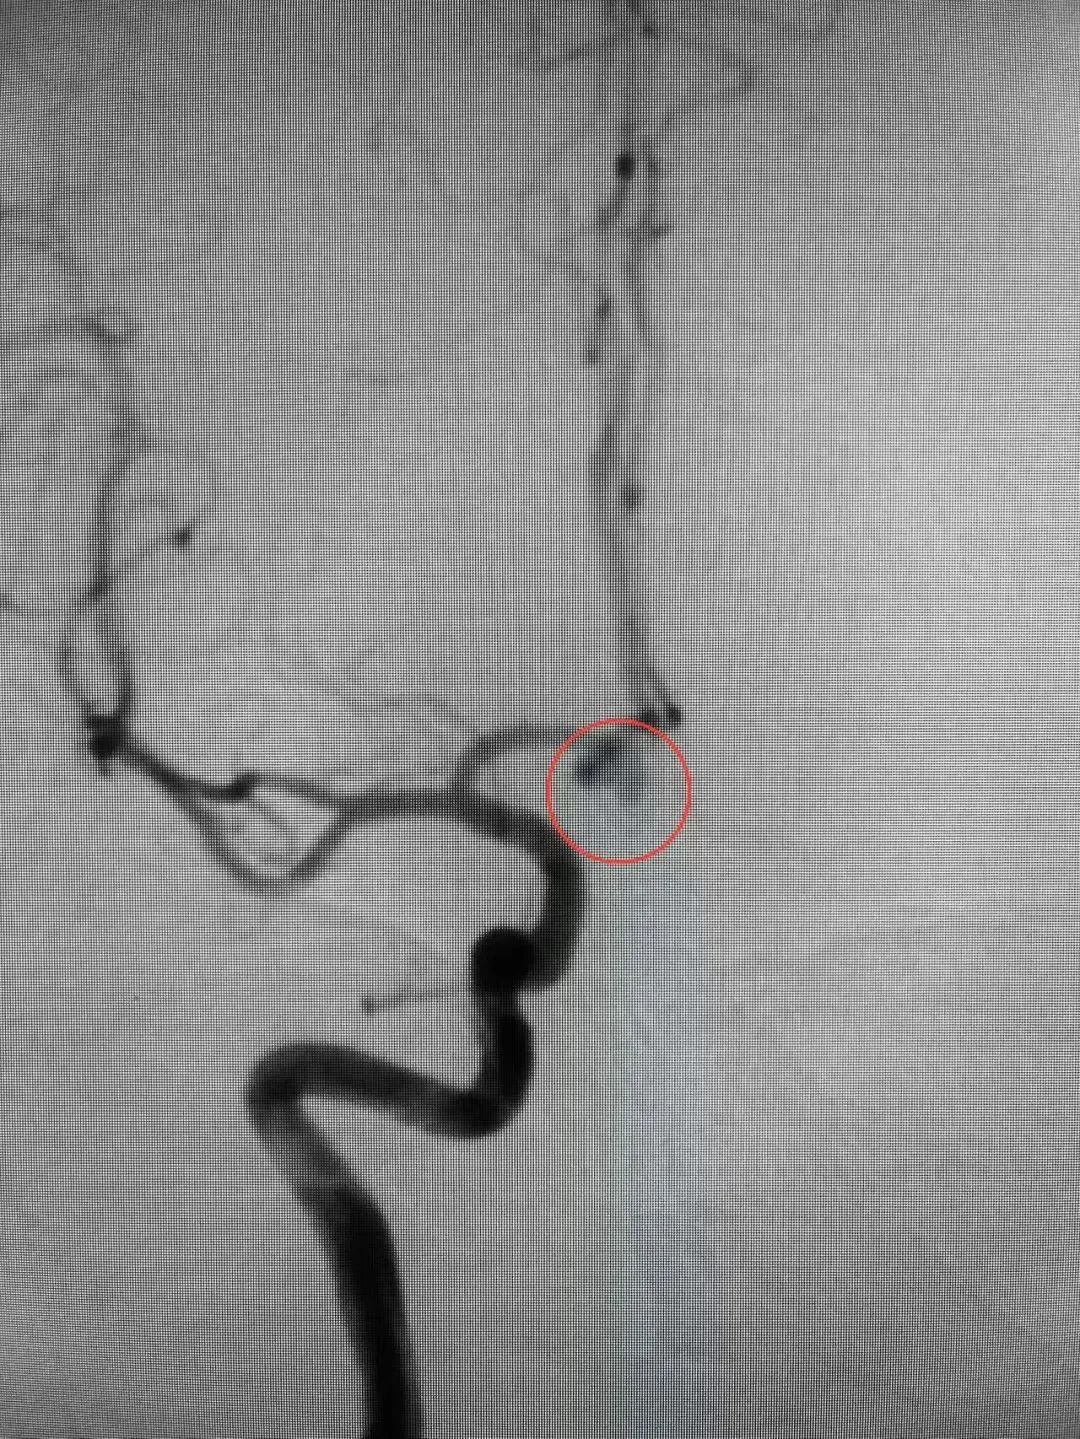

近日,殷女士在家中突发头痛,随后意识丧失,被家人送至我院急诊科。医生迅速安排颅脑CT扫描等相关检查。结果显示蛛网膜下腔出血,CTA显示前交通动脉瘤。情况紧急,我院脑病科过智伟医生考虑殷女士此次发病与动脉瘤破裂有关,前交通动脉瘤破裂死亡率高达30-40%,死亡风险高,需立即手术处理。在与殷女士家属进行充分沟通,详细解释了病情和治疗方案后,医护团队立即实施了急诊局麻下全脑血管造影+全麻颅内动脉瘤栓塞术。手术造影过程中,发现造影剂外渗,动脉瘤仍在持续出血,死亡率随之提高。医护团队沉着冷静,最终成功排除了殷女士脑中的这颗“不定时炸弹”。

△术前△ △术后△